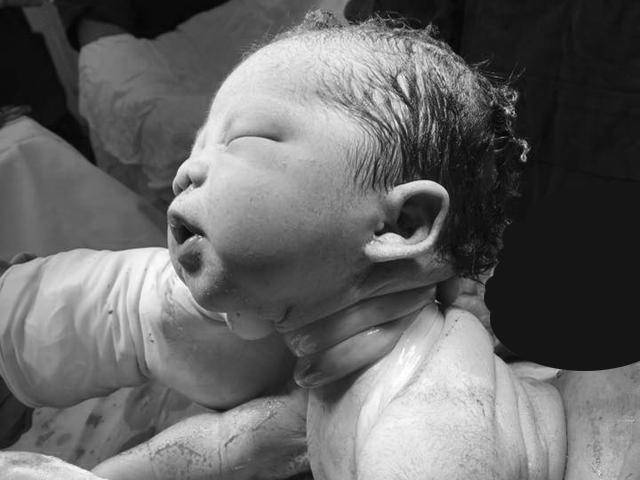

Hình ảnh em bé chào đời với dây rốn quấn chặt quanh cổ khiến nhiều người xem hốt hoảng.

Gần đây, trên các trang mạng xã hội, hình ảnh một em bé chào đời với 5 vòng dây rốn quấn chặt cổ và một nút thắt đang được chia sẻ rầm rộ. Đặc biệt, tuy ở trong hoàn cảnh đó nhưng em bé chào đời thông qua một ca sinh thường hoàn toàn tự nhiên và sau sinh vẫn khỏe mạnh bình thường.

Bức ảnh được chia sẻ rầm rộ trên các trang mạng xã hội.

"5 vòng dây rốn quanh cổ

1 nút thắt ở dây rốn.

1 ca sinh hoàn toàn bình thường.